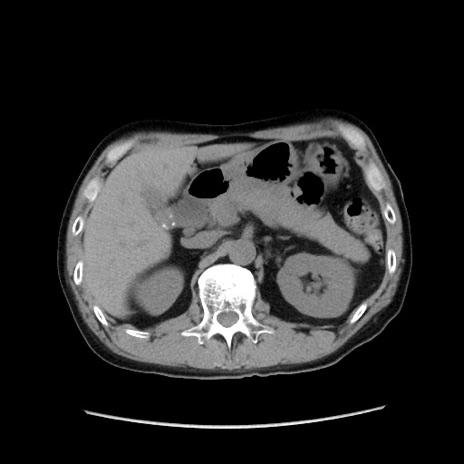

症例37(横断像)

【症例】40歳代 男性

【主訴】腹痛

【現病歴】4時間ほど前に電車に乗車中に臍部上より腹痛出現。徐々に増悪し起立困難となり、救急外来受診。生ものは数日食べていない。今朝お雑煮を食べた。

【身体所見】BT 36.8℃、BP 117/84mmHg、HR 91/min、SpO2 97%、苦悶様、腹部:臍上部広範囲圧痛あり、反跳痛±

【データ】WBC 8100、CRP 0.03